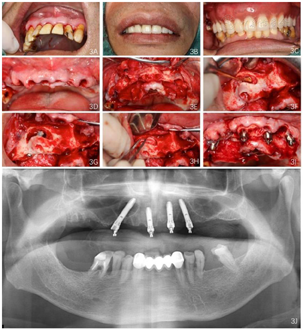

种植方案设计:拟在12、22位点植入2颗轴向植体,15、25位点植入2颗倾斜植体,13区颊侧开窗,剥离上颌窦底黏膜,15倾斜植体通过上颌窦间隔,达鼻底皮质骨层,利用双皮质骨固定种植体。

(1)种植一期手术:①阿替卡因肾上腺素注射液局麻下拔除上颌余留牙。②沿16-26区域牙槽嵴顶全层翻瓣,清除拔牙窝内炎性肉芽组织,平整牙槽嵴顶。③分别于12、22、25区定点,逐级备洞,12、22植入Nobel Speedy 4.0 mm×13 mm种植体;25近中倾斜植入Nobel Speedy 4.0 mm×15 mm种植体;④超声骨刀于13、14、15牙槽嵴顶8 mm处行唇、颊侧骨壁近远中向开窗,开窗面积约15 mm×8 mm,剥离上颌窦底黏膜后,15区定点,推开上颌窦底黏膜,近中倾斜备洞直达鼻底,倾斜植入Nobel speedy 4.0×18 mm种植体。⑤4颗种植体初期稳定性均达到35NCm,15颊侧骨开窗区种植体表面覆盖浓缩生长因子(Concentrated growth factor, CGF)(视频4)。⑥拔除18,12旋入RP17°3 mm复合基台,22旋入RP17°4 mm复合基台,15、25分别旋入RP 30°5 mm复合基台,修整牙龈组织,黏膜瓣复位、缝合创口,拍摄曲面体层片(图3)。

(2)即刻修复:制取上下颌硅橡胶印模,利用术前可摘局部义齿转移颌位关系,制作丙烯酸树脂临时固定义齿,咬合关系恢复至第二前磨牙,调整咬合。口内固定修复螺丝加力至15N.CM,牙龈硅橡胶封闭螺丝孔,拍摄曲面体层片(图4,图5)。